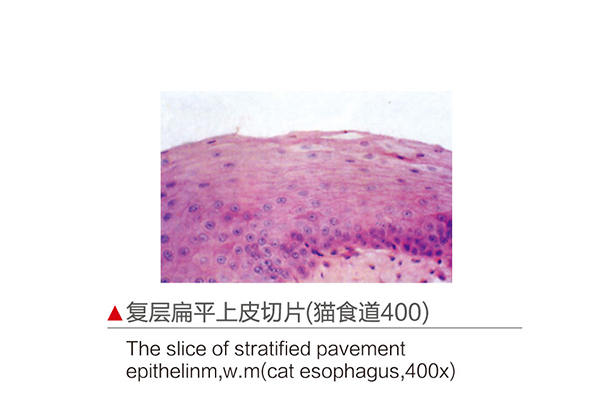

推荐产品

苏模苏医教的产品结构精确细微细致,说明详细,是理想的直观教具。